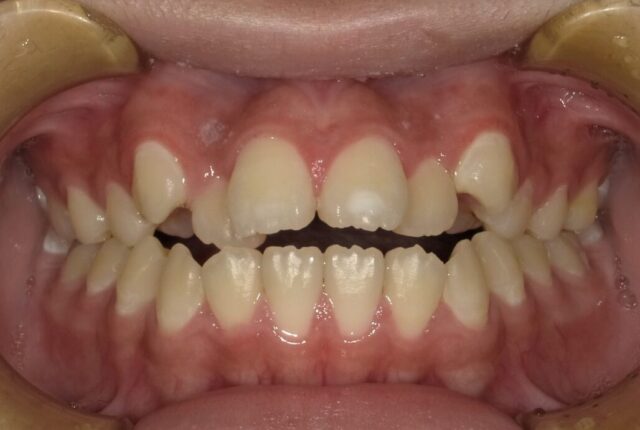

《動的治療期間1年8ヶ月》

before

after

| 診断名 | 上顎前歯部叢生を伴う下顎前突 開咬 |

| 初診時年齢・性別 | 10歳8ヶ月・女子 |

| 治療期間 | 1段階目:5カ月 経過観察:1年 2段階目:20ヶ月~ |

| 治療方法・治療内容 | 1段階目:フェイシャルマスク 2段階目:ストレートワイヤーテクニック |